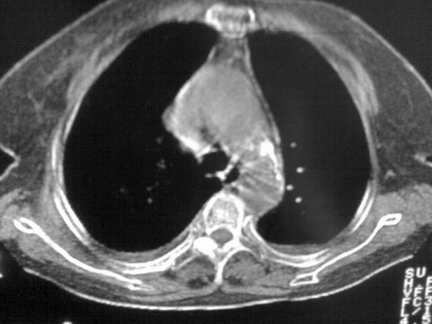

标题: CT13142:女 80 胸闷、气短、1w [打印本页]

标题: CT13142:女 80 胸闷、气短、1w

右肺炎性变,双侧甲状腺肿,胸膜肥厚。

右肺炎性变

双侧胸腔积液

缩窄性心包炎

左室为主的心脏增大。

胸膜肥厚,

右肺感染;双侧胸腔少量积液,心影增大,可能与心功不全有关;胸内甲状腺肿。

右肺炎性变,双侧甲状腺肿,胸膜肥厚,心影增大考虑心功能不全.

胸内甲状腺肿;右肺感染;双侧胸腔少量积液。

胸内甲状腺肿;右肺中叶感染;双侧胸腔少量积液;心影增大,考虑有心功能不全。